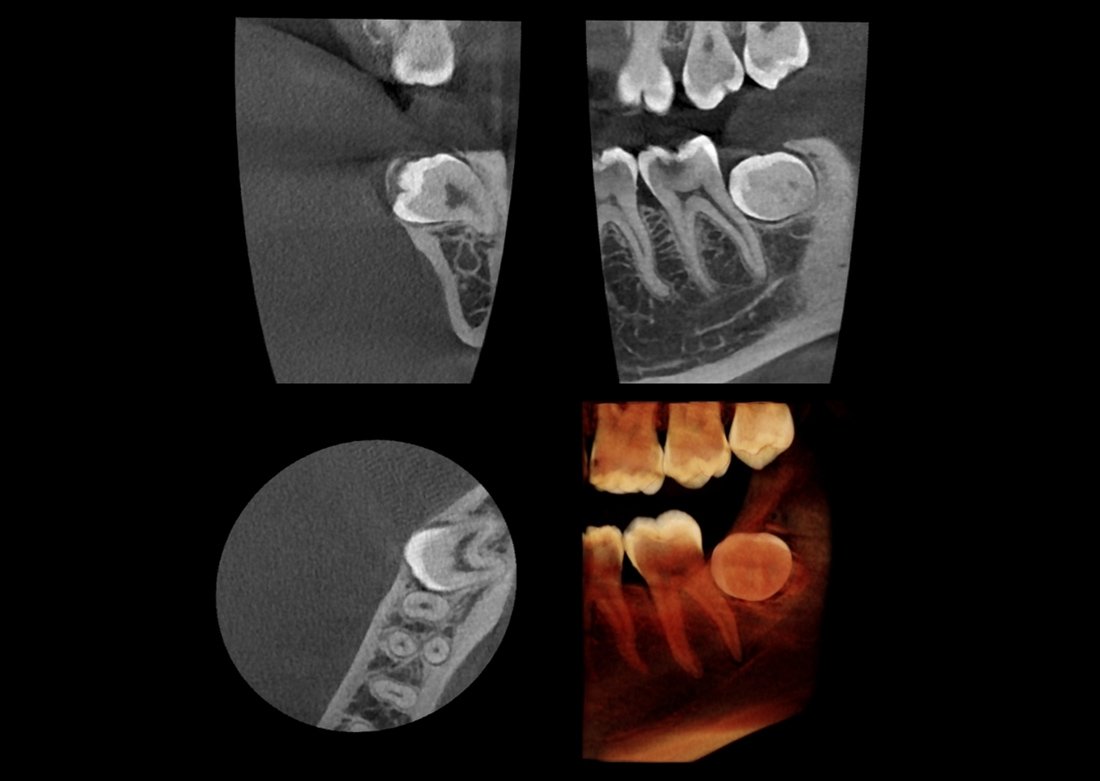

SMARF™

(Smart Metal Artifact Reduction Function)

Minimalizálja a fém okozta torzulásokat, így a protézisek sem rontják a képminőséget, és optimális felvételek készíthetők.

KLİNIKAI KÉPEK

Kiváló diagnosztikai képalkotás több éves tapasztalattal és szakértelemmel.

A Genoray büszkesége, amelyet világszerte elismernek és szeretnek.